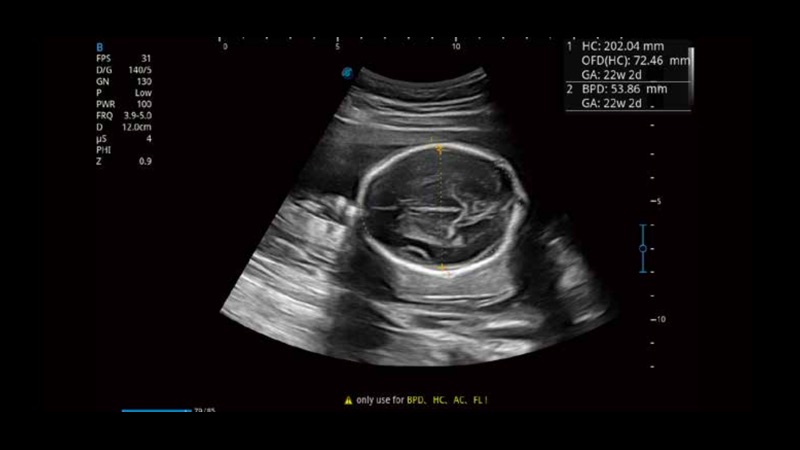

S-Fetus基于大數(shù)據(jù)深度學(xué)習(xí)算法,能夠幫助您在產(chǎn)前篩查過程中智能識(shí)別胎兒標(biāo)準(zhǔn)切面、自動(dòng)測(cè)量并錄入報(bào)告。一個(gè)按鍵,即可智能、精準(zhǔn)、高效地獲取胎兒生理指標(biāo),極大簡(jiǎn)化您的產(chǎn)科檢查操作。

可快速對(duì)產(chǎn)科掃查切面完成胎兒生理學(xué)參數(shù)的自動(dòng)測(cè)量,減少操作者按鍵次數(shù),大幅提升檢查效率。